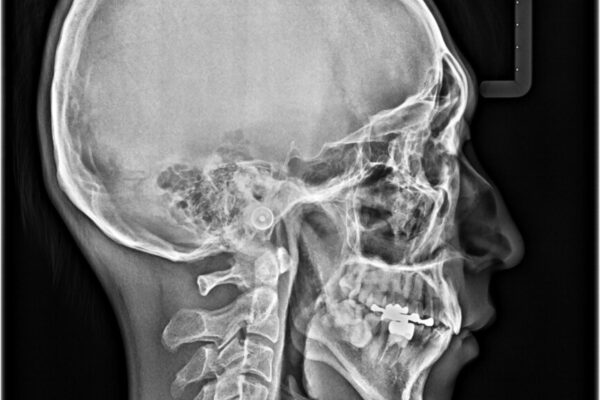

治療前

• 口元の突出感を改善!目立ちにくいワイヤー矯正で自信を持てる自然な横顔に 治療前画像

精密検査の結果、上下左右の小臼歯4本を抜歯し、そのスペースに前歯を後方へ移動させる矯正治療をご提案しました。

装置は、透明感のあるクリアブラケットとホワイトコーティングされたワイヤーを使用した、目立ちにくい審美装置を選択。

周囲に気づかれにくく、日常生活にも自然に溶け込みます。